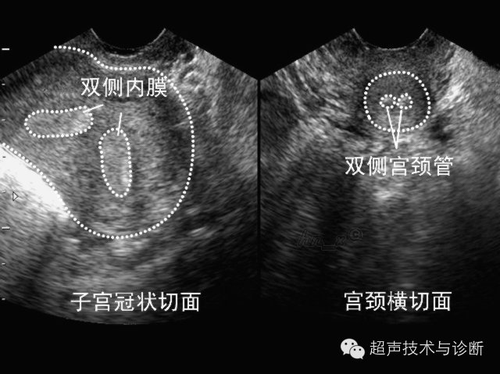

子宫纵膈是一种子宫异常的疾病,简单来说,就是在女性的子宫里有一个纵膈将子宫分开,许多人都不太清楚子宫纵膈的具体症状是什么,子宫纵膈的临床表现有以下几种: